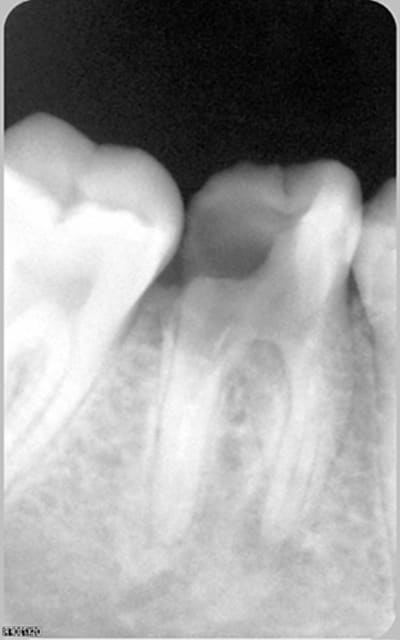

Beaucoup moins drôle et de la même:

patiente de 18 ans avec une 46 "qu'on n'arrive pas à refermer" depuis février et peut-être vue avant et ignorée. Antibios, huiles essencielles et j'en passe certainement...

Bin voilà ce sera extraction de toute façon. :-(